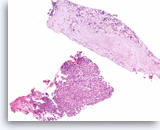

Ductal adenocarcinoma #1,

Pancreas FNA, Direct Smear.

The aspirates show single and clusters of malignant epithelial cells. The clusters are three-dimensional with overlapped nuclei. A few histiocytes are seen in the background.

20X

Ductal adenocarcinoma #1,

Pancreas FNA, Direct Smear.

The aspirates show single and clusters of malignant epithelial cells. The clusters are three-dimensional with overlapped nuclei. A few histiocytes are seen in the background.

20X